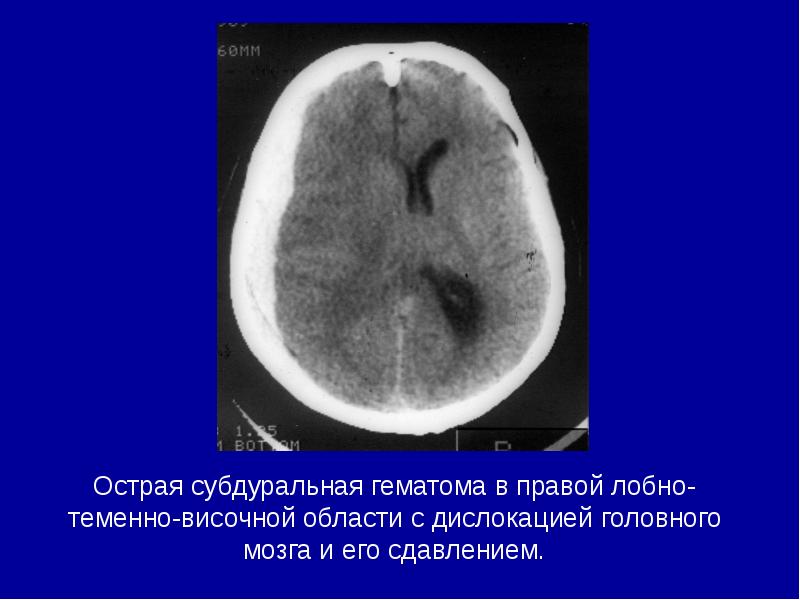

- 11. Острая субдуральная гематома в правой лобно-теменно-височной области с дислокацией головного мозга